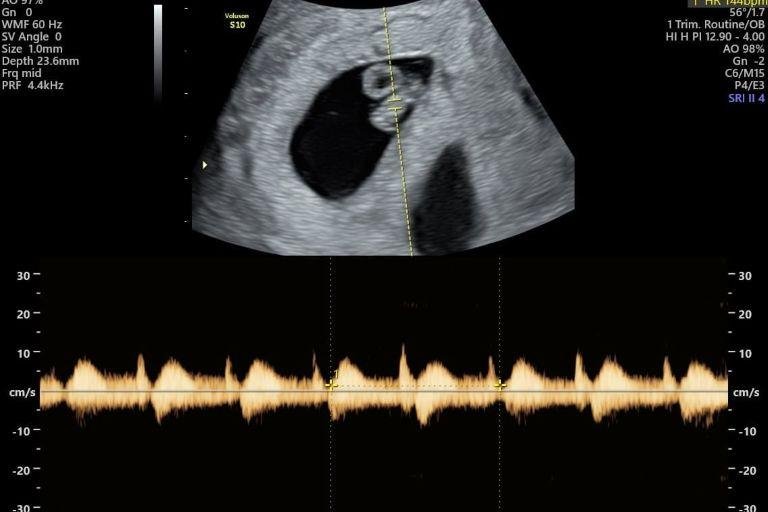

• Ultrassom Obstétrico

Acompanhamento completo da gestação com exames de alto e baixo risco, incluindo ultrassom obstétrico simples, com Doppler, Doppler com perfil biofísico fetal (PBF) e ultrassom morfológico do 1º, 2º e 3º trimestre.